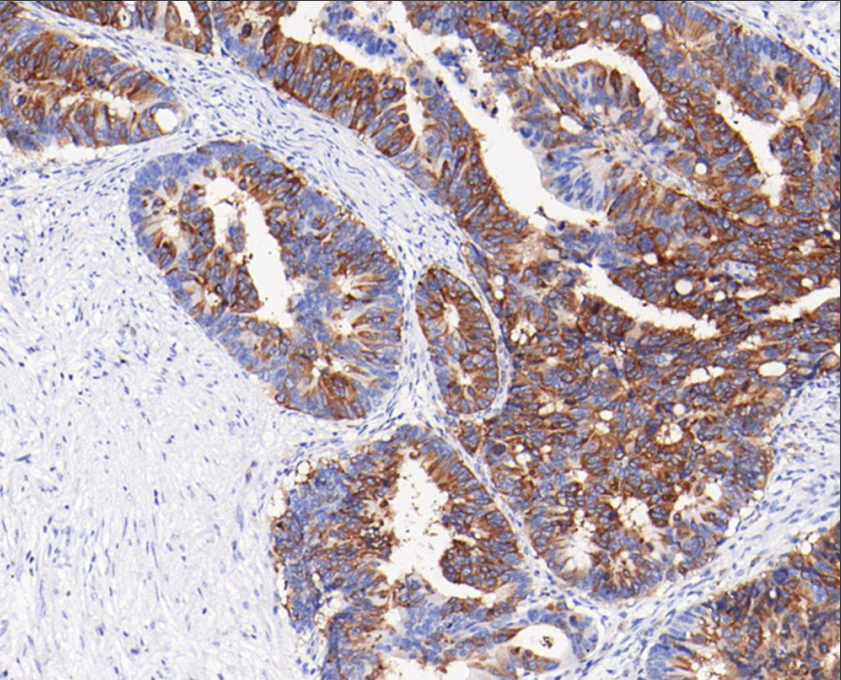

Cellular localization: cytoplasm/membrane

Tissue: paraffin section

The nucleoside diphosphate reductase large subunit (RRM1) is one of two distinct subunits that make up nucleoside diphosphate reductase. During the S phase of the cell cycle, prior to DNA synthesis, RRM1 catalyzes the production of deoxyribonucleotides. Numerous studies have shown that RRM1 controls cell proliferation through the production of deoxyribonucleotides and controls the metastatic tendency of cancer cells through PTEN induction. In NSCLC, RRM1 expression is highly correlated with ERCC and PTEN expression, and RRM1-positive tumors indicate slow progression.

The RRM1 antibody reagent specifically binds to the RRM1 molecular antigen. The immunohistochemistry kit containing the RRM1 antibody reagent is suitable for assessing tumor resistance to gemcitabine in cancers such as non-small cell lung cancer and ovarian cancer.